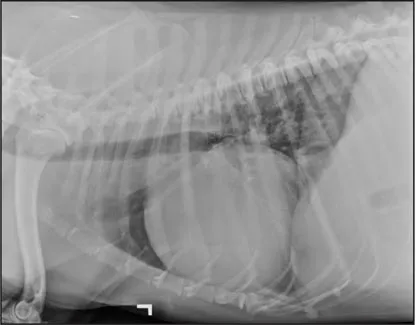

CASE 1.1 A 7-year-old neutered male Labrador Retriever who was hit by a car. You obtain these thoracic radiographs: Figs. 1.1a, b, left and right lateral projections, respectively; Figs. 1.1c, d, ventrodorsal and dorsoventral projections, respectively.

1.1a